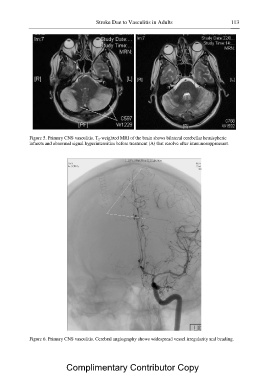

Page 137 - The Vasculitides Volumes 2